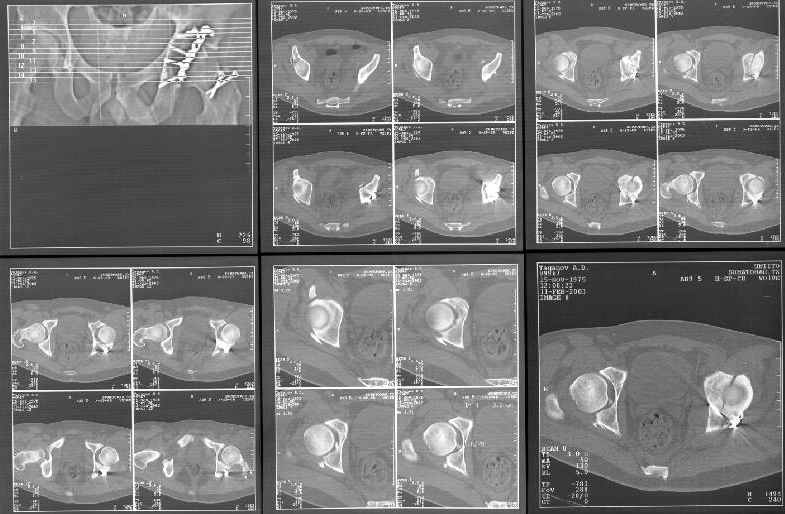

Пациент переведен в нашу клинику на 5 день после множественной травмы 25.01.2003 - двустороннее повреждение вертлужных впадин, разрыв левого крестцово-подвздошного сочленения. Вывихи обоих бедер. В месте первичного поступления подвздошный вывих правого бедра вправлен 26.01.2003, наложено вытяжение за левую вертельную область. Остеосинтез левой вертлужной впадины выполнен у нас 6.02.2003. Вопрос: надо ли синтезировать задне-верхний край правой вертлужной впадины?

правую впадину собрали здорово! Мои поздравления Рункову. Сами меня учили-учили, а где же запирательная проекция левой вертлужной

впадины. Такое впечатление что на КТ есть интерпозиция кусочком, тогда уж точно надо туда залесть, а так, я считаю не стоит.

Уважаемый Алексей, через месяц после повреждения обострять травму, чтобы продлить "колясочный" срок? Второй сустав станет опорным не скоро.Головка на Ртг концентрически вставлена, задний фрагмент не интерпонирует, лимбус,по видимому тоже, ямочный фрагмент мешать не должен,герметизирующую манжету адекватно восстановить, обычно, не удается. Выгоды от оперативного вмешательства сомнительны. Я бы оперировать не стал.Еще месяц без нагрузки (по меньшей мере) и в нашей "конторе"- МОНИКИ(Вы наверняка знаете О.Ш.Буачидзе) положились бы на ощущения пациента при активных движениях правым бедром. Можно и сейчас проверить на возможность блокады и тогда принимать окончательное решение.

Если нагрузка на конечности будет не ранее 5-6 недель,оперировать не стоит. Считаю, что эндопротезирование справа не будет нужным.